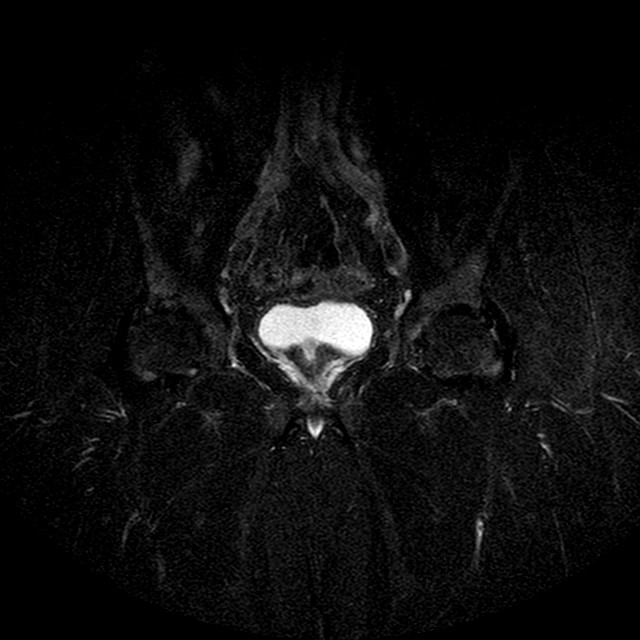

STIR

Evidenti e simmetriche alterazioni osteofitosiche in regione coxo femorale con riduzione delle rime articolari. Degenerazione completa del cercine glenoideo. Non attuali segni di versamento articolare. Non segni di edema osseo che escludono attuale algodistrofia od osteonecrosi. Lieve e simmetrica riduzione del trofismo della muscolatura glutea.